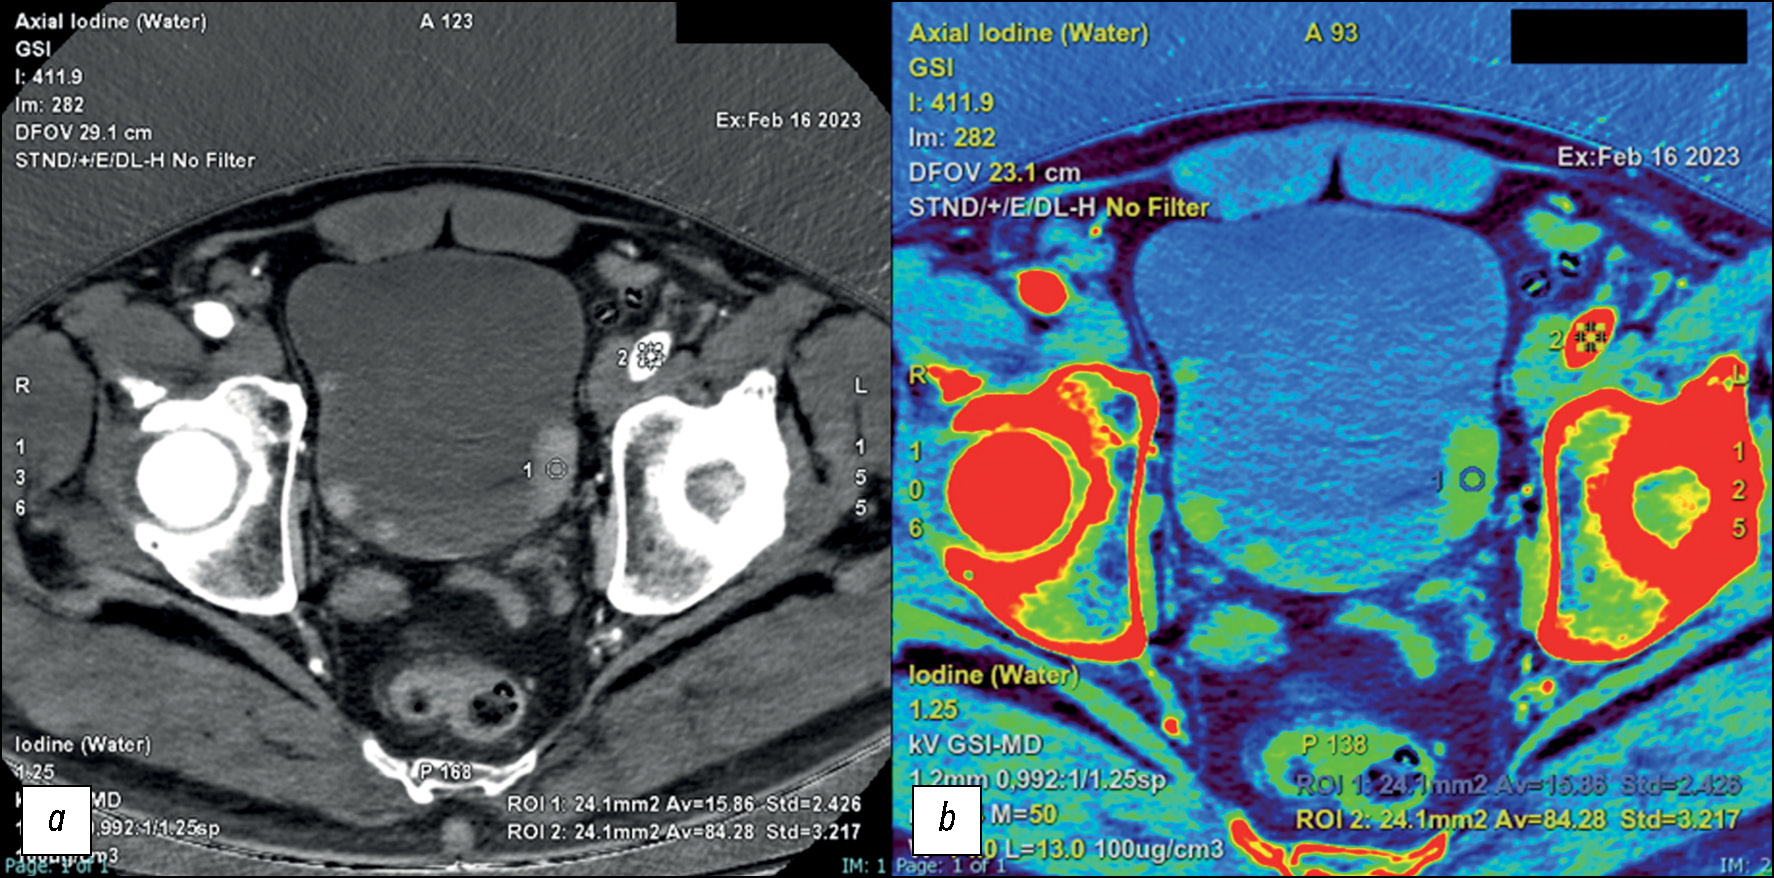

Йодная карта

С помощью сложного алгоритма можно выбрать материал с определёнными характеристиками затухания и получить изображение определённого материала. Например, выбрав материал с высоким уровнем затухания, такой как йод, можно получить изображение участков контрастирования йодом — йодную карту [31].

В отличие от изображения с удалёнными участками контрастирования йодом, на йодной карте отображаются все участки поглощения йода. Таким образом, такой вид постобработанного изображения позволяет подсчитать количество йода в миллиграммах на миллилитр (мг/мл) [14, 32].

Затем данные о плотности йода, как правило, накладываются в виде цветной карты на стандартные КТ-снимки, при этом значения вокселя представляют концентрацию йода в мг/мл. Йодная карта позволяет разграничить сосудистые и несосудистые очаги. Количественное определение йода и его нормализация по количеству йода, присутствующего в аорте, позволяет косвенно измерить степень васкуляризации исследуемой области. Оптимальные пороговые значения для различения сосудистых и несосудистых поражений зависят от типа платформы ДЭКТ: 0,5 мг/мл для dsDE; 1,3 мг/мл для rsDE и 0,5 мг/мл для dlDE [31, 33].

При исследовании участков поглощения йода и его отсутствия можно использовать йодные карты для определения количества йода в каждом вокселе, чтобы таким образом обнаружить небольшие участки контрастного усиления для установления характеристик очага. Йодные карты также можно использовать для разграничения сосудистых и несосудистых поражений, тоже с целью установления характеристик очага. В этом случае в нефрографической фазе количественное определение йода следует нормализовать по содержанию йода в аорте. Порог концентрации йода ≥1,0 мг/мл демонстрирует высокую чувствительность (92%) для уротелиальных опухолей. Высокая специфичность (92%) исследования может быть достигнута при пороговом значении ≥3,0 мг/мл (рис. 6–8) [42].

Рис. 8. Компьютерная томография в нефрографической фазе. Её целесообразно использовать для количественной оценки концентрации йода и её нормализации по содержанию йода в аорте: a — йодная карта с демонстрацией нескольких твёрдых узелков на стенке мочевого пузыря; b — йодная карта с наложением цвета для более качественной визуализации очагов. Среднее значение на очаг составляет 1,5 мг/мл, значение Av подвздошной артерии — 8,4 мг/мл, а пороговое значение — 1,3 мг/мл.

Таким образом, можно утверждать, что йодная карта, полученная с помощью ДЭКТ, информативнее стандартной КТ, поскольку позволяет установить количество йода в очаге и более надёжно измерить степень контрастирования очага. Её можно использовать в качестве суррогатного маркёра поглощения контрастного вещества тканями, учитывая, что на неё не влияет собственное затухание ткани, и она не требует оценки истинно контрастированного изображения до и после введения контрастного вещества. Во втором случае для описания очага необходимо выполнить несколько сканирований после введения контраста, включая сканирование артерий и портальной вены [14].